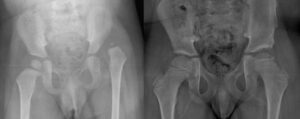

Knee surgery in arthrogryposis

Knee deformities are present in approximately 70% of children with classic arthrogryposis , presenting with flexion or extension deformities.

Knee flexion deformity in arthrogryposis

For flexion deformities, interventions may include:

- release of the soft tissues (hamstrings, posterior capsule) followed by possible progressive gypsotomies, i.e. progressive corrections in plaster using corrective stages

- distal femoral extension osteotomies

- gradual corrections with Ilizarov external fixator

- progressive corrections with anterior epiphysiodesis of the distal femur. These procedures have been used more frequently in recent years for these conditions, but their efficacy is still uncertain.

- In cases where cutaneous pterygia are present , collaboration with plastic surgeons is useful to treat both the skin component and the joint deformity component.

Knee extension deformity in arthrogryposis

For extension deformities (recurvatum, subluxation, dislocation), possible interventions include, after an adequate period of non-surgical treatment:

- quadricepsplasty using an inverted V-shaped anterior approach

- anterior capsulotomy with reduction of dislocation